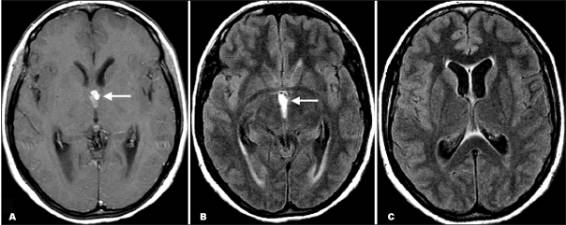

Hình ảnh trên phim chụp cộng hưởng từ cũng là công cụ hữu ích để chẩn đoán ATSL thể thần kinh và có thể tốt hơn cả chụp cắt lớp CT để phát hiện các thương tổn trong não tủy, trong cuống não, trong não thất. Việc áp dụng nó nên cân nhắc khi CT không chẩn đoán ra. CT và siêu âm là rất nhạy để phát hiện các tổn thương ATSL tại mắt và hệ cơ xương.

Trả lời: Liên quan đến câu hỏi của bạn, chúng tôi xin phúc đáp rằng hiện có rất nhiều bệnh ký sinh trùng ký sinh và gây bệnh ở người, một trong những cơ quan mà bị các tác nhân gây bệnh này ký sinh chính là hệ thần kinh trung ương (CNS), bên cạnh đó chúng có thể ký sinh và gây bệnh ở gan, thận, tim, da, niêm mạc, mắt, tai mũi họng, sinh dục, tiết niệu,…Khi bị nhiễm và gây bệnh ở hệ thần kinh trung ương, các ký sinh trùng có thể khiến sinh ra các triệu chứng như chị bạn đang có: chẳng hạn như mờ mắt, mù mắt, nhìn mờ, nhìn đôi, nhức đầu không điển hình, ù tài, nôn, buồn nôn, nôn mửa, đau cơ, động kinh, co giật,…Nhân câu hỏi của bạn, chúng tôi xin trình bày có bạn một số ca bệnh tương đối điển hình cùng với một số tác nhân gây bệnh từ ký sinh trùng đã được nhóm bác sĩ chuyên điều trị về bệnh giun sán ở hệ thần kinh trung ương tại Trung tâm Medic thành phố Hồ Chí Minh đã phát hiện, chẩn đoán và điều trị nhiều năm qua:

5. Võ Thị Thu M. ♀, 53t, làm ruộng 18/06/2005 | Migrain, cơn dày / lồi mắt (P) + nhiều răng sâu Từ 2 tháng | MRI : TT điểm rải rác 2 thùy trán, tăng tín hiệu trên T2 + Flair | STRONGYLOIDE TOXOCARA GNATHOSTOMA | ALBENDAZOLE (2 đợt) + kháng sinh | RẤT TỐT 6 tháng |